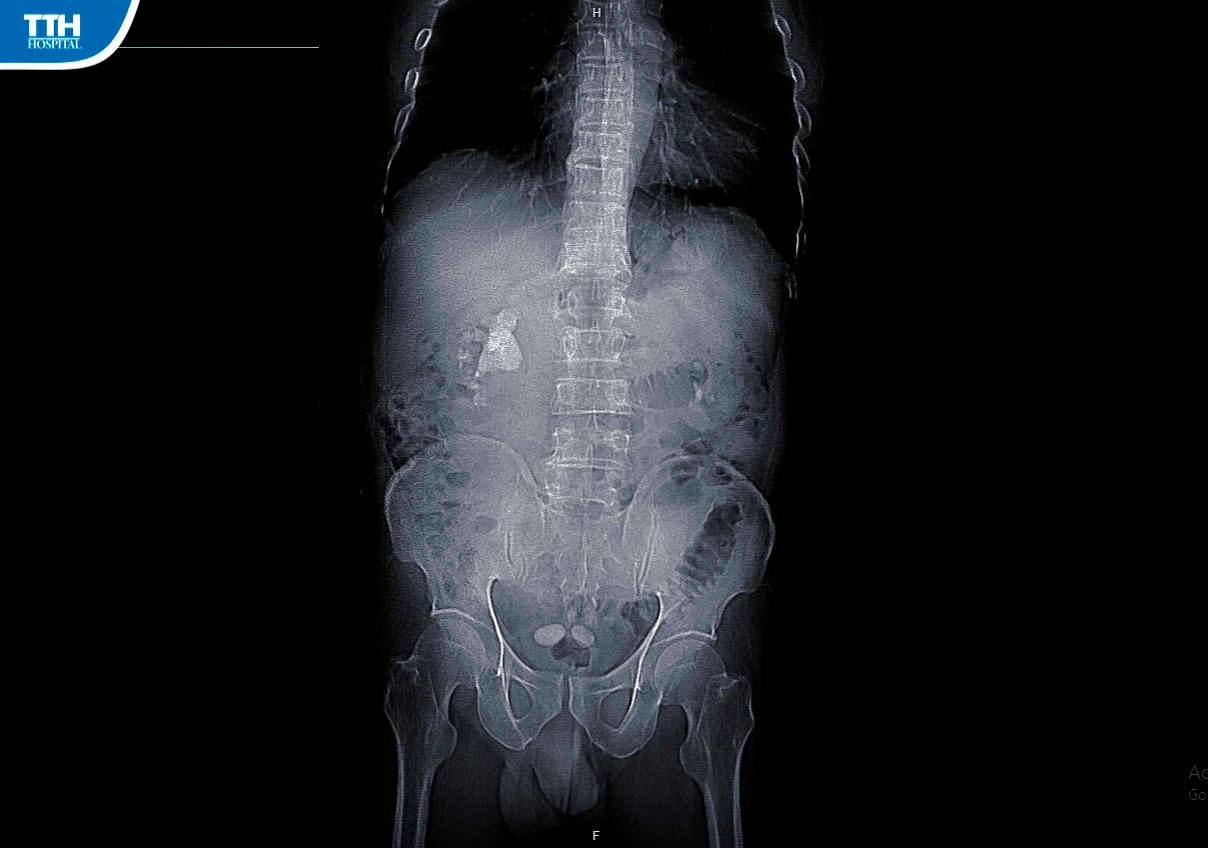

Vừa qua, Bệnh viện Đa khoa TTH Hà Tĩnh đã phẫu thuật lấy sỏi san hô thận phức tạp cho bệnh nhân P.N.A (57 tuổi, Hà Tĩnh). BN cho biết: ‘‘Tôi đã phát hiện trong cơ thể có sỏi từ lâu nhưng không muốn điều trị bằng phương pháp phẫu thuật nên đã chữa bằng phương pháp dân gian. Gần đây, tôi thấy đau quặn hông lưng bên phải kèm theo tiểu buốt, tiểu lắt nhắt ngày một nhiều nên quyết định đến Bệnh viện Đa khoa TTH Hà Tĩnh để thăm khám và điều trị. Tại đây, Tôi được các Bác sĩ thăm khám kỹ càng và cho chụp phim cắt lớp vi tính. Bác sĩ chẩn đoán tôi có sỏi san hô phức tạp ở thận phải và chỉ định mổ mở lấy sỏi thận’’.